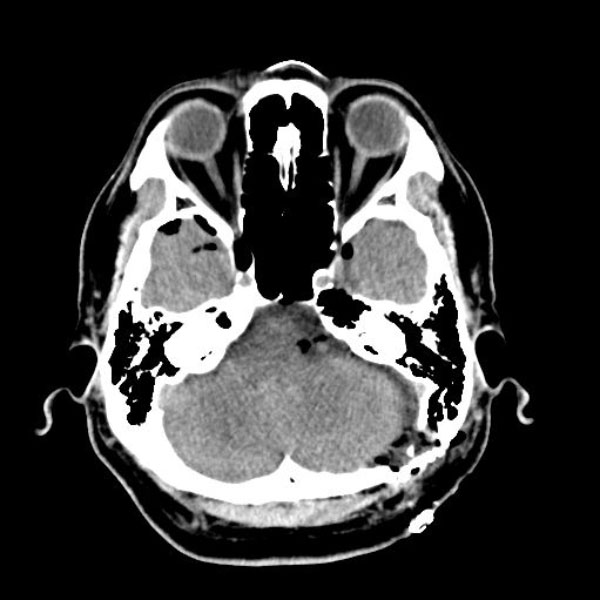

手術後

(CT)